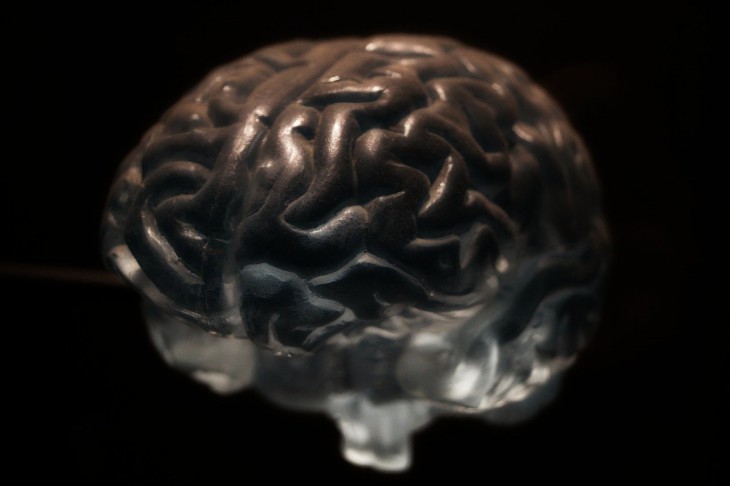

Исследователи начали ряд научных изысканий, связанных с восстановлением нейронов мозга у людей после инсульта.

Ученые нейробиологи подготовили несколько экспериментальных исследований, которые могут выявить механизм, позволяющий восстановить мозгу утраченные клетки и нейронные связи.

Это значит, что в перспективе могут быть разработаны персонифицированные подходы.

Они смогут стимулировать данные процессы и ускорять возвращение пациентов к нормальной жизни. Кроме того, ученые замечают, что после ишемического инсульта примерно пять миллионов человек остаются инвалидами.

Учитывается также, что из вышеуказанных пятнадцати миллионов человек со всего мира шесть погибает от перенесенной ситуации. В целом же, нейропластичность головного мозга дает возможности к восстановлению органа, однако скорость и уровень реабилитации у всех разные.